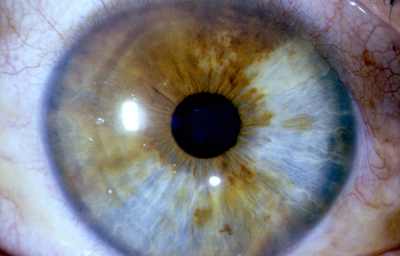

En la cara Anterior esta el pigmento que le da el color al Iris y dependiendo del grado de reabsorción u atrofia de esa capa anterior se pueden observar:

Las Criptas de Fuchs: que son pequeñas aberturas alrededor del collarete, producto de la atrofia o reabsorción de la hoja anterior del iris, que le permiten al estroma y a los tejidos mas profundos estar en contacto con el humor acuoso.

Cuando el Iris no tiene criptas, se considera que la reabsorción u atrofia de la hoja anterior (memb. pupilar) se detuvo en el circulo menor.

La Heterocromia Iridis y la Heterocromia Parcial o Sectorial

Son variantes, en la que un Iris es completamente diferente en color al Iris del otro ojo, o un Iris tiene un sector de diferente color a otro sector; es poco común y frecuentemente se asocia con enfermedades oculares, pero existen en los humanos como variantes normales.